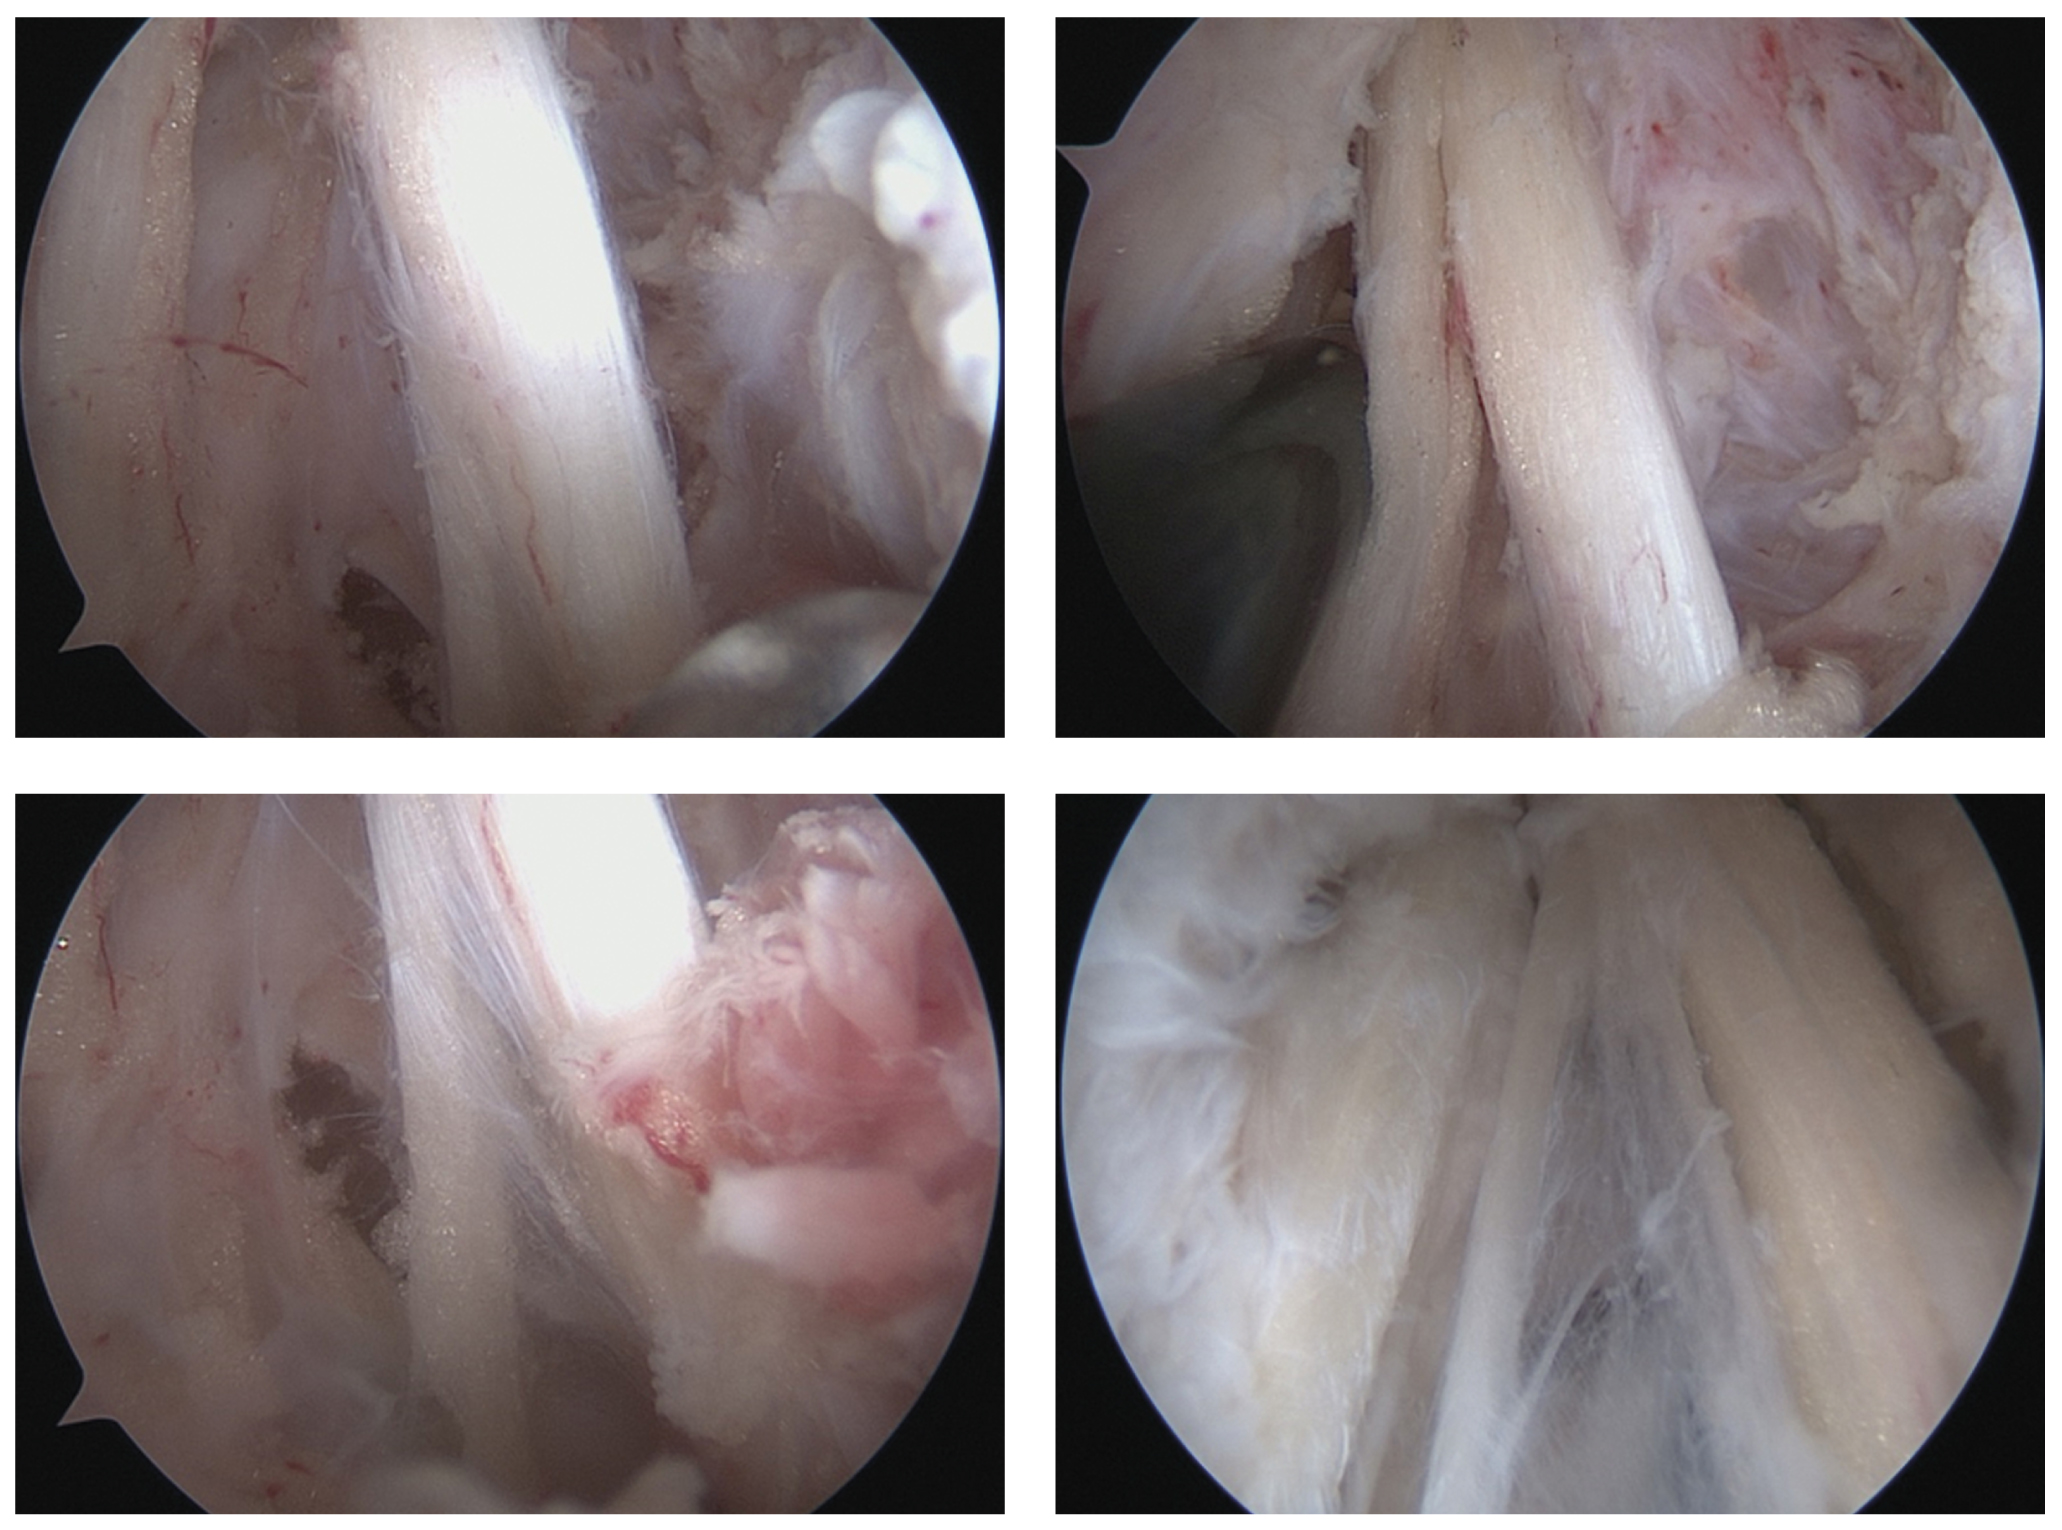

По завершении санации полости сустава приступали к выполнению доступа к подмышечному нерву. Артроскоп переводили в область нижнего кармана плечевого сустава. Под контролем спинальной иглы выполняли дополнительный задненаружный доступ (рис. 4). По направлению иглы формировали рабочий порт, в который вводили рабочий инструмент (рис. 5). Доступ к подмышечному нерву осуществляли за счет рассечения нижней капсулы сустава и последовательного разделения рубцовых тканей (рис. 6).

Рис. 4. Задненаружный доступ к плечевому суставу: a — введение спинальной иглы в проекции задненаружного доступа; б — визуализация кончика иглы в суставе на мониторе. / Fig. 4. Posterior access to the shoulder joint: a — introduction of a spinal needle in projection of postero-lateral portal; б — viewing on monitor of a needle tip in a joint.

Рис. 5. Расположение артроскопа и рабочего инструмента при выполнении невролиза. / Fig. 5. Position of an arthroscope and an instrument during nerve decompression.

Рис. 6. Рассечение нижней капсулы плечевого сустава и доступ к подмышечному нерву. / Fig. 6. Inferior capsulotomy and axillary nerve approach.

Во всех случаях было выявлено сдавление подмышечного нерва грубой рубцовой тканью. С целью его декомпрессии проводили наружный невролиз в этой области (рис. 7).

Рис. 7. Подмышечный нерв и отходящие ветви после выполнения невролиза. / Fig. 7. Axillary nerve and its branches after performing the decompression.